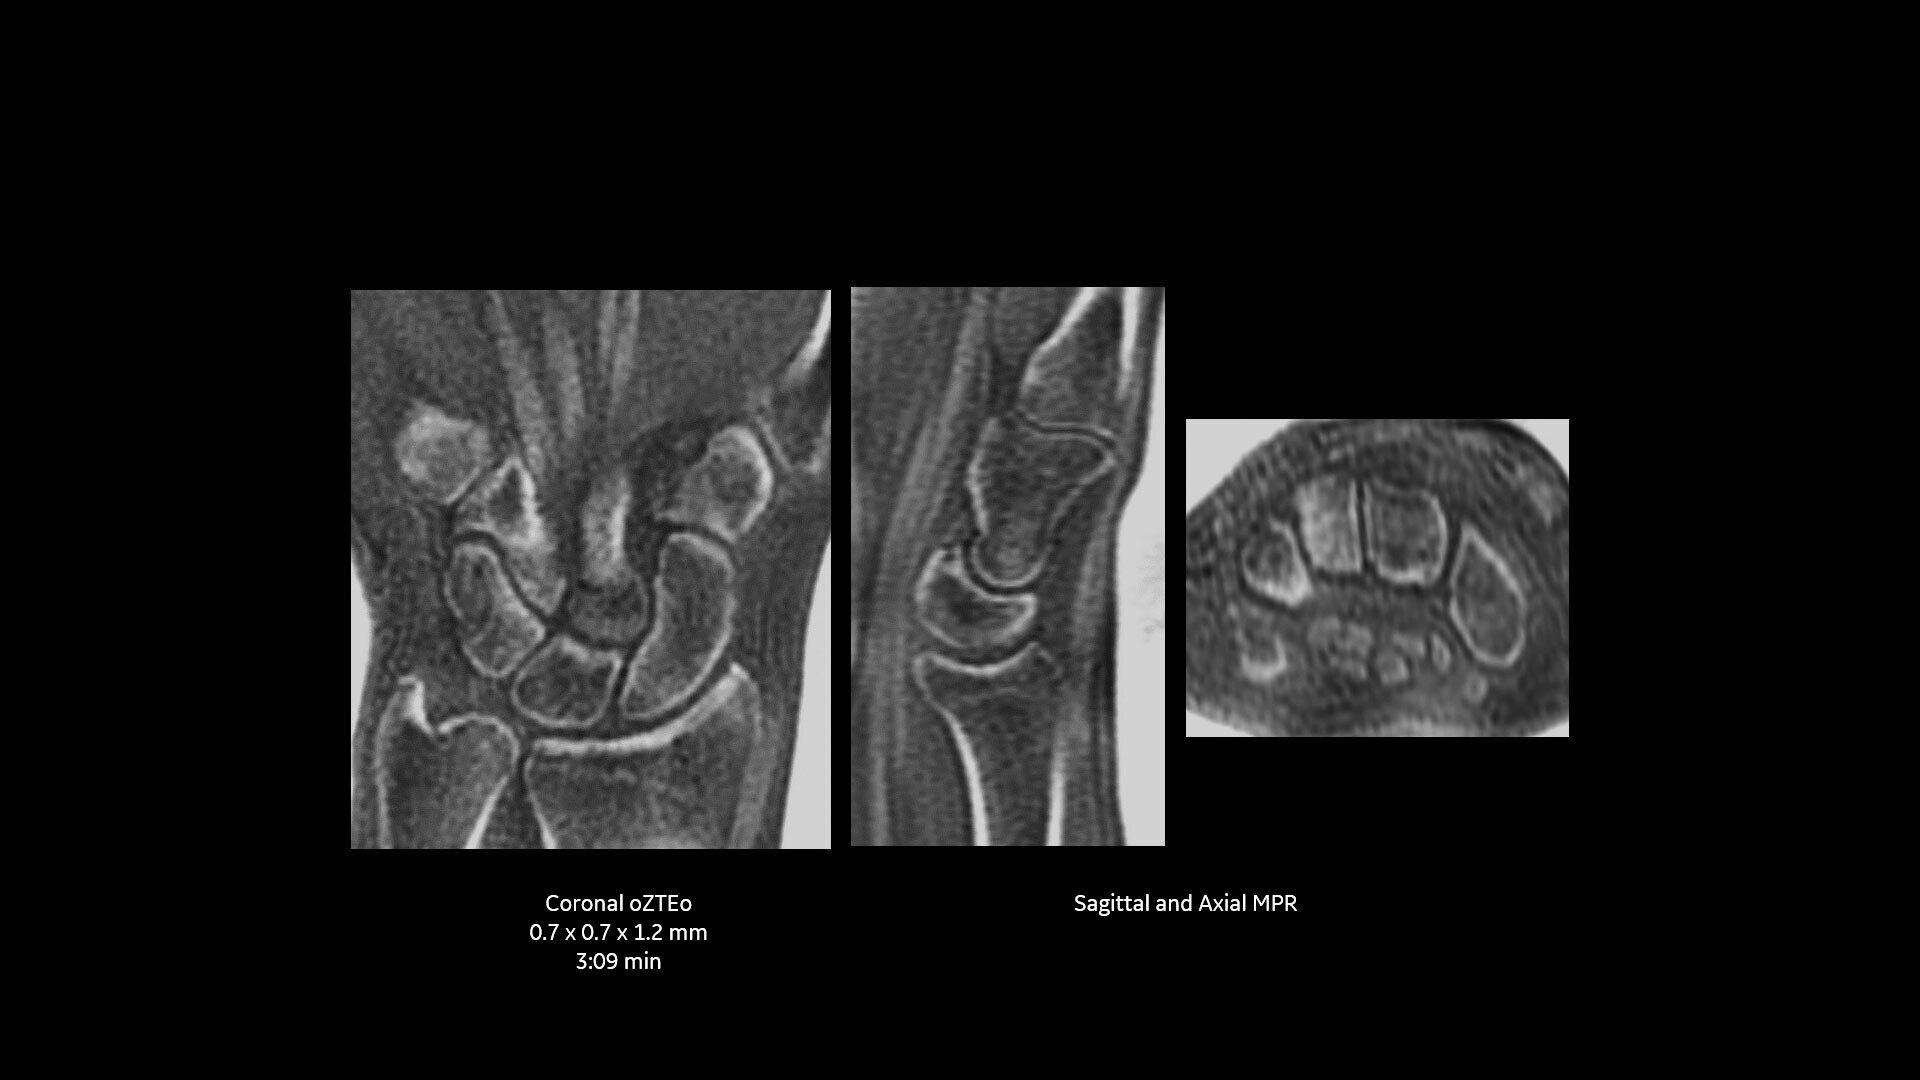

Available for all anatomies without ionizing radiation, oZTEo delivers images of bone morphology, calcification, ossification and fractures. oZTEo complements conventional MR soft tissue exams with perfect co-registration and provides 3D isotropic imaging using a radial ZTE acquisition, with inherent motion insensitivity. Use oZTEo with Volume Illumination for realistic 3D rendering.